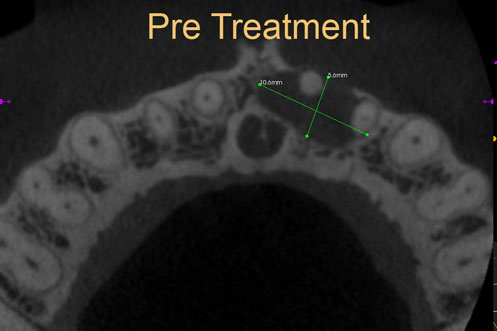

Cyst Enucleation